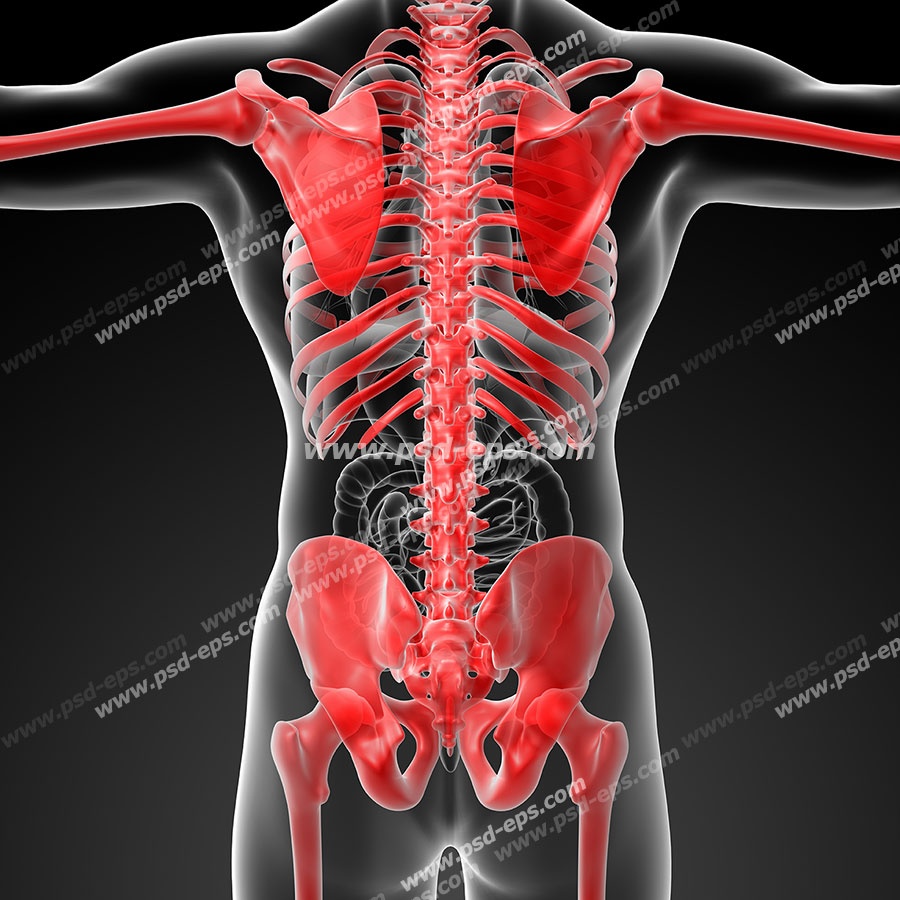

آناتومی سه بعدی بدن انسان عکس گرافی بدن.

اسکلت داربست بدن است تمام قسمت های بدن روی اسکلت قرارگرفته اند بدن انسان از ۲۰۶ قطعه استخوان تشکیل شده است این استخوان ها طوری با نظم کنار هم قرار گرفته اند که انسان را قادر می سازد حرکات دقیقی داشته باشد. استخوان یک نسج بسیار محکم است زیرا در ترکیب آن منرالها مانند کلسیم و دیگر وجود. اسکلت داربست بدن است تمام قسمت های بدن روی اسکلت قرارگرفته اند بدن انسان از ۲۰۶ قطعه استخوان تشکیل شده است این استخوان ها طوری با نظم کنار هم قرار گرفته اند که انسان را قادر می سازد حرکات دقیقی داشته باشد. آناتومی سه بعدی بدن انسان عکس گرافی بدن امعاء و احشاء بدن آناتومی سه بعدی بدن انسان عکس گرافی بدن امعاء و احشاء بدن قلب کبد روده.